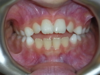

Cas 2

Enfant de 8 ans présentant un important décalage horizontal entre les 2 mâchoires corrigé avec un appareil amovible.